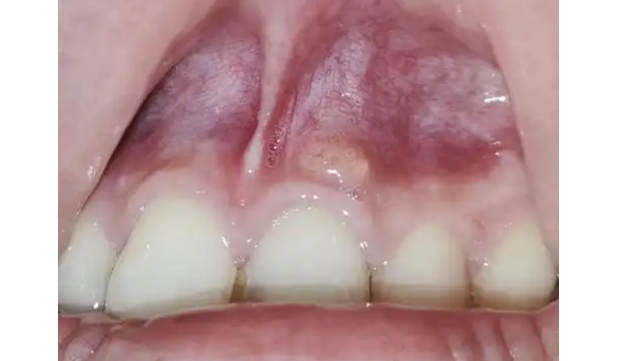

牙齿旁边长脓包的主要原因是牙髓感染引起的牙周脓肿。当口腔卫生不良或牙齿遭受外伤时,细菌可能会侵入牙髓(牙齿内部的血管和神经组织)。细菌感染会引起炎症,导致脓液的积聚。随着压力逐渐增大,脓液会向外排出,形成牙齿旁的脓包。

牙齿旁边长脓包的症状通常包括:

(1) 长期的牙龈肿胀和红肿。

(2) 牙龈疼痛,尤其是在咀嚼食物或碰触牙龈时。

(3) 牙齿松动或移位。

(4) 卫生用具蘸取脓液后味道难闻。